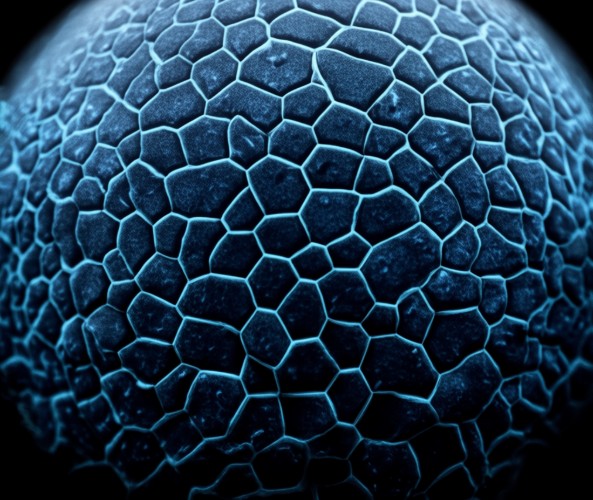

8. 角膜大小和形态检查

用途:评估角膜大小、弯曲度等

方法:测量横径(约11mm)、垂直径(约10mm),观察弯曲度

特点:可判断是否为圆锥角膜(令患者向下看,角膜顶点将下睑中央部顶起)

2. 评估圆锥角膜

通过角膜地形图分析、弯曲度检查等,判断是否为圆锥角膜

在自然光线下观察角膜弯曲度,让患者向下看,观察角膜顶点是否将下睑中央部顶起